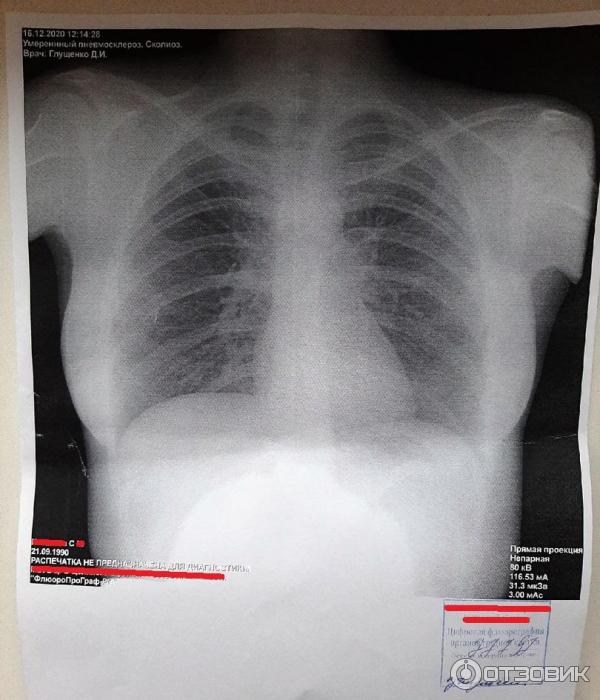

Что такое малоконтрастная рентгенограмма органов грудной клетки